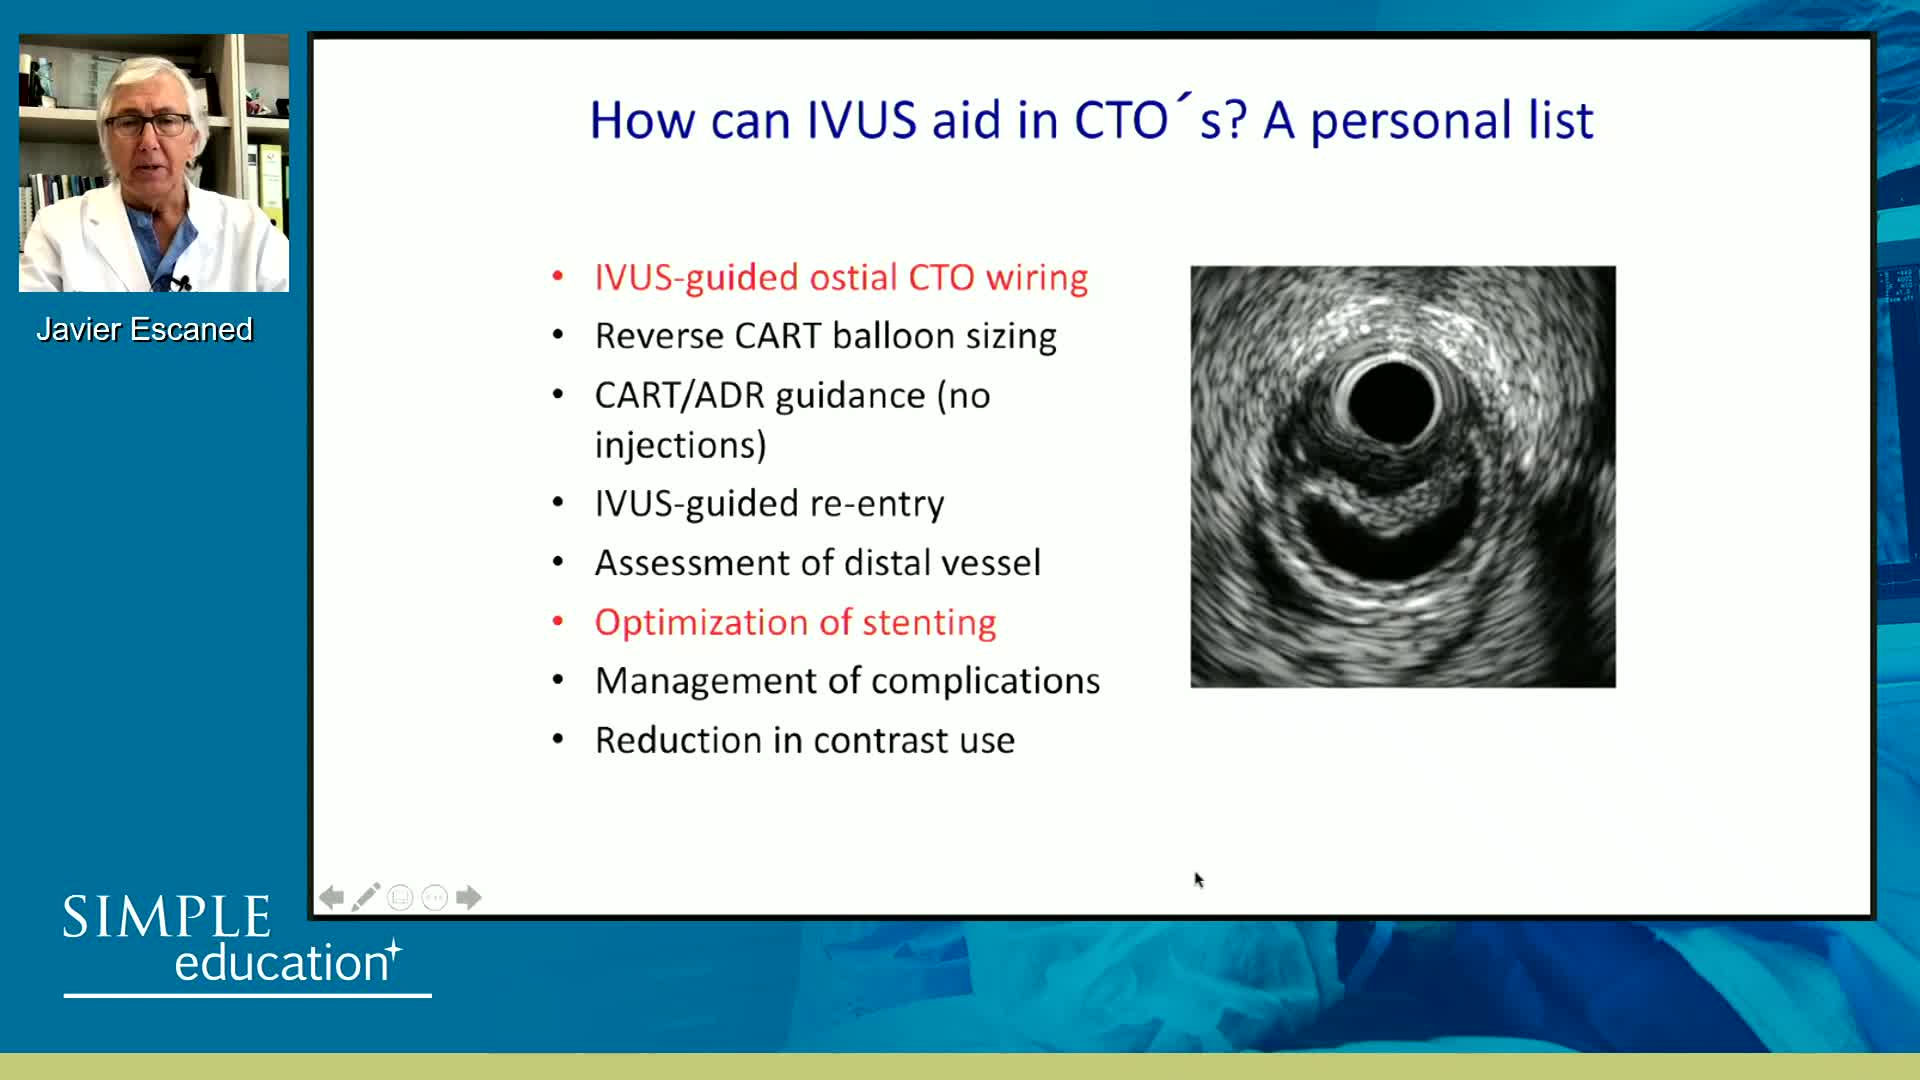

Best practices and personalised medicine in complex PCI - Prof Javier Escaned

How to perform good co-registration measurements using iFR and IVUS - Prof Carlo Di Mario